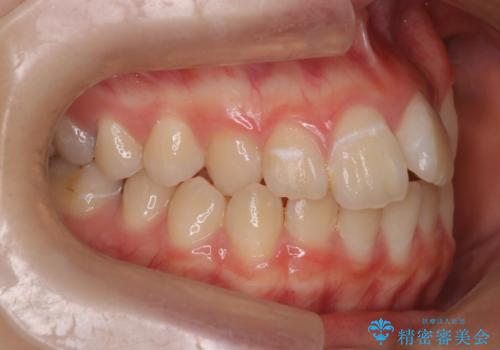

マウスピース矯正で前歯のガタツキを改善! 短期間で治療完了

- 前歯のガタツキが気になるとのことで来院されました。

前歯のガタツキに加え、奥歯の噛み合わせにも問題があったため、マウスピース矯正で治療し改善しました。